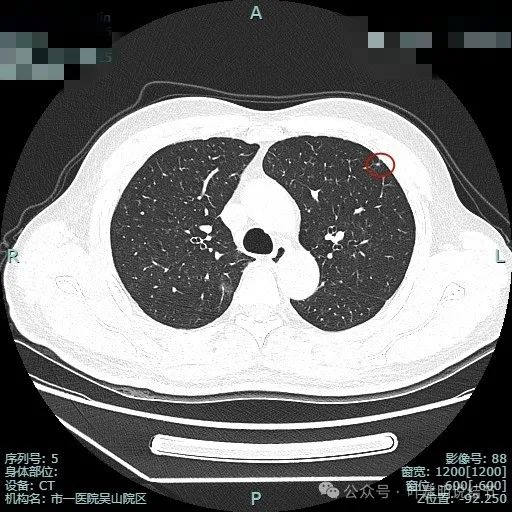

图片

次病灶术前定位,上图均是定位胶,结节太小,在其附近层面。